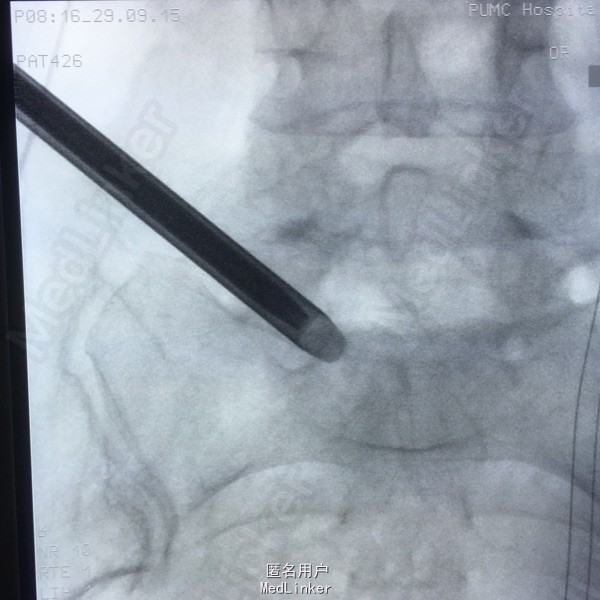

65岁女性,右下肢放射性疼痛2年半,保守治疗效果不佳 2年前曾行C5-6的ACDF术。

L5-S1左侧棘旁压痛(+),右小腿外侧针刺觉稍弱,右侧跟腱反射稍弱。 腰椎CT提示L5-S1间盘突出,偏右侧。 腰椎X线片提示髂嵴偏高,L5横突肥大。

L5-S1椎间盘突出 C5-6 ACDF术后 拟行椎间孔镜手术

因为穿刺通道比较狭小,进入椎间盘时偏杨氏,采用由内而外的方式减压神经根,用镜下弹性弯钳较好完成了神经根减压。